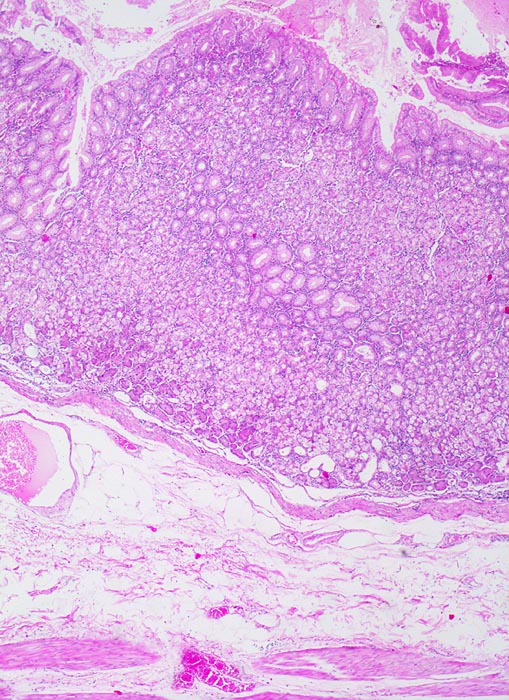

Die ersten beiden Typen entsprechen histologisch meist einem intestinalen Typ nach Lauren (> 1342). Diese Tumoren sind scharf begrenzt, bilden tubuläre oder papilläre Strukturen wie die Dickdarmkarzinome, sind meist assoziiert mit bekannten umweltbedingten Risikofaktoren und haben eine bessere Prognose.

Beim diffusen Typ nach Lauren infiltrieren Einzelzellen oder Zellstränge, meist mit Siegelringzellanteilen diffus die Magenwand. Eine Drüsenbildung ist nicht erkennbar. Dieser Tumortyp tritt bei relativ jungen Patienten auf und ist mit genetischen Faktoren assoziiert (positive Familienanamnese). Wegen des diffus infiltrativen Wachstums ohne makroskopisch sicher erkennbare Grenze müssen diese Tumoren mit einem grösseren Sicherheitsabstand operiert werden. Siegelringkarzinome machen rund 20% aller Magenkarzinome aus.

Adenokarzinome können tubuläre, papilläre, muzinöse, siegelringzellige und undifferenzierte Anteile aufweisen, wobei die beiden letzteren besonders aggressive Tumoren darstellen.